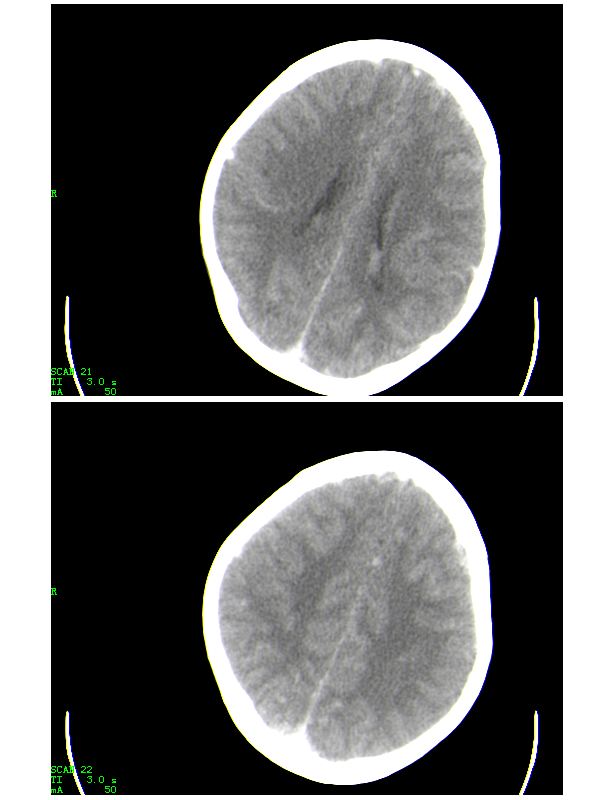

下面是第二天的复查和受伤后第五天的复查,左侧硬膜下血肿有所吸收,脑内条状高密度无改变

第五天的复查片

导致的原因楼上的战友已经讲的非常好了,再加深点印象

人体血液中影响ct值的主要成分是有形成分红细胞和血浆中的蛋白质,尤其室含铁的hb,其占血液中蛋白质总量的大部分,亦是引起血液ct密度变化的主要因素。hb含量与ct值间具有相关性,noman等的研究表明hb含量每改变10g/l,相应ct值变化为1.86hu。

本病主要应与蛛网膜下腔出血相鉴别,鉴别要点:

(1)高密度血管网络旁仍见清晰、正常低密度脑脊液影;

(2)临床没有急性颅内出血的症状何体征。